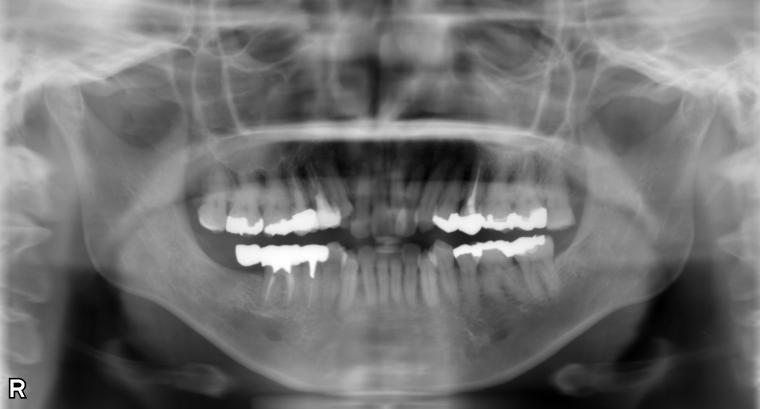

下顎大臼歯1本欠損症例

49歳女性/下1本欠損/インプラント埋込手術

右下第二大臼歯は欠損していたため、マウスピース矯正で歯列を整えてから、インプラントを1本埋入しました。